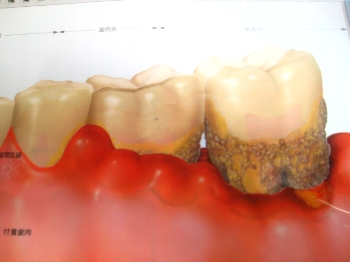

歯の周りにはこのように、歯周ポケットという “ ポケット ”があります。

いわゆるポケットです。

歯周病菌で骨が溶かされると、この歯周ポケットは深くなります。

深くなったポケットは、いっぱい食べかすを溜め込みます。

溜め込んだ食べかすは、細菌の餌になりどんどん毒素を出していきます。

綺麗にシャンプー(歯磨き)をして、汚れを綺麗に落としてからリンス(デンタルリンス)をしましょうね。

そうすると効果が期待できますよ。